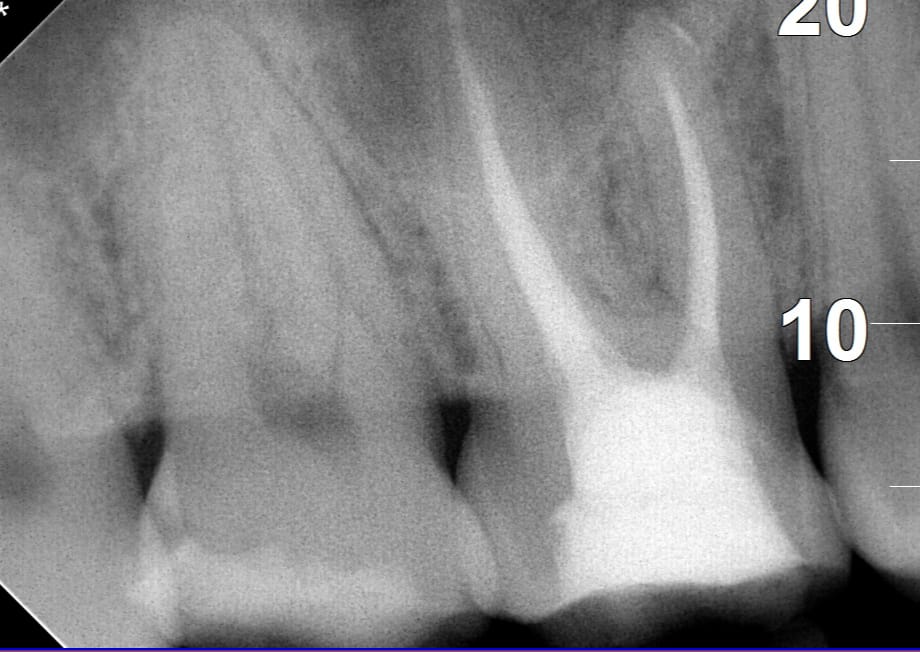

Endodoncia en Quito: cómo salvar un diente y eliminar el dolor dental

El dolor dental intenso suele ser una señal de que algo no está bien en…